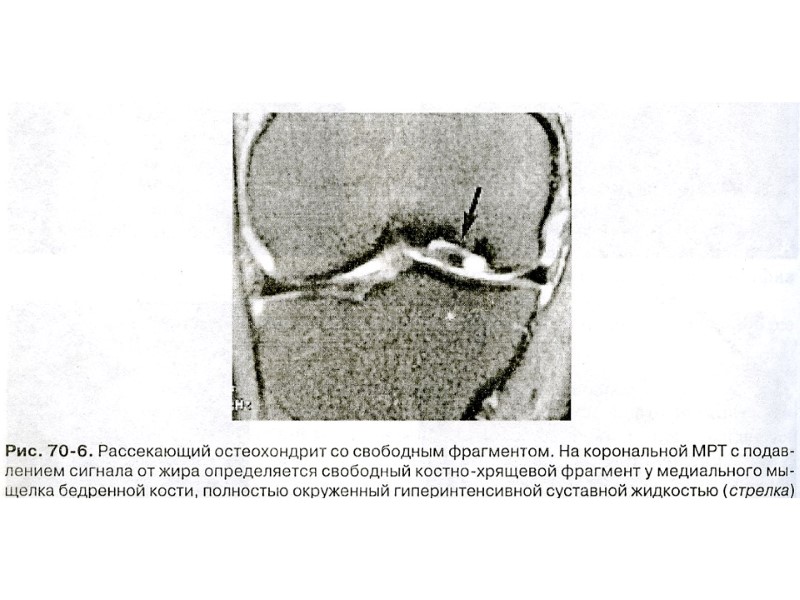

Пневмоартрограмма коленного сустава Добавочные внутрисуставные образования (мыши)